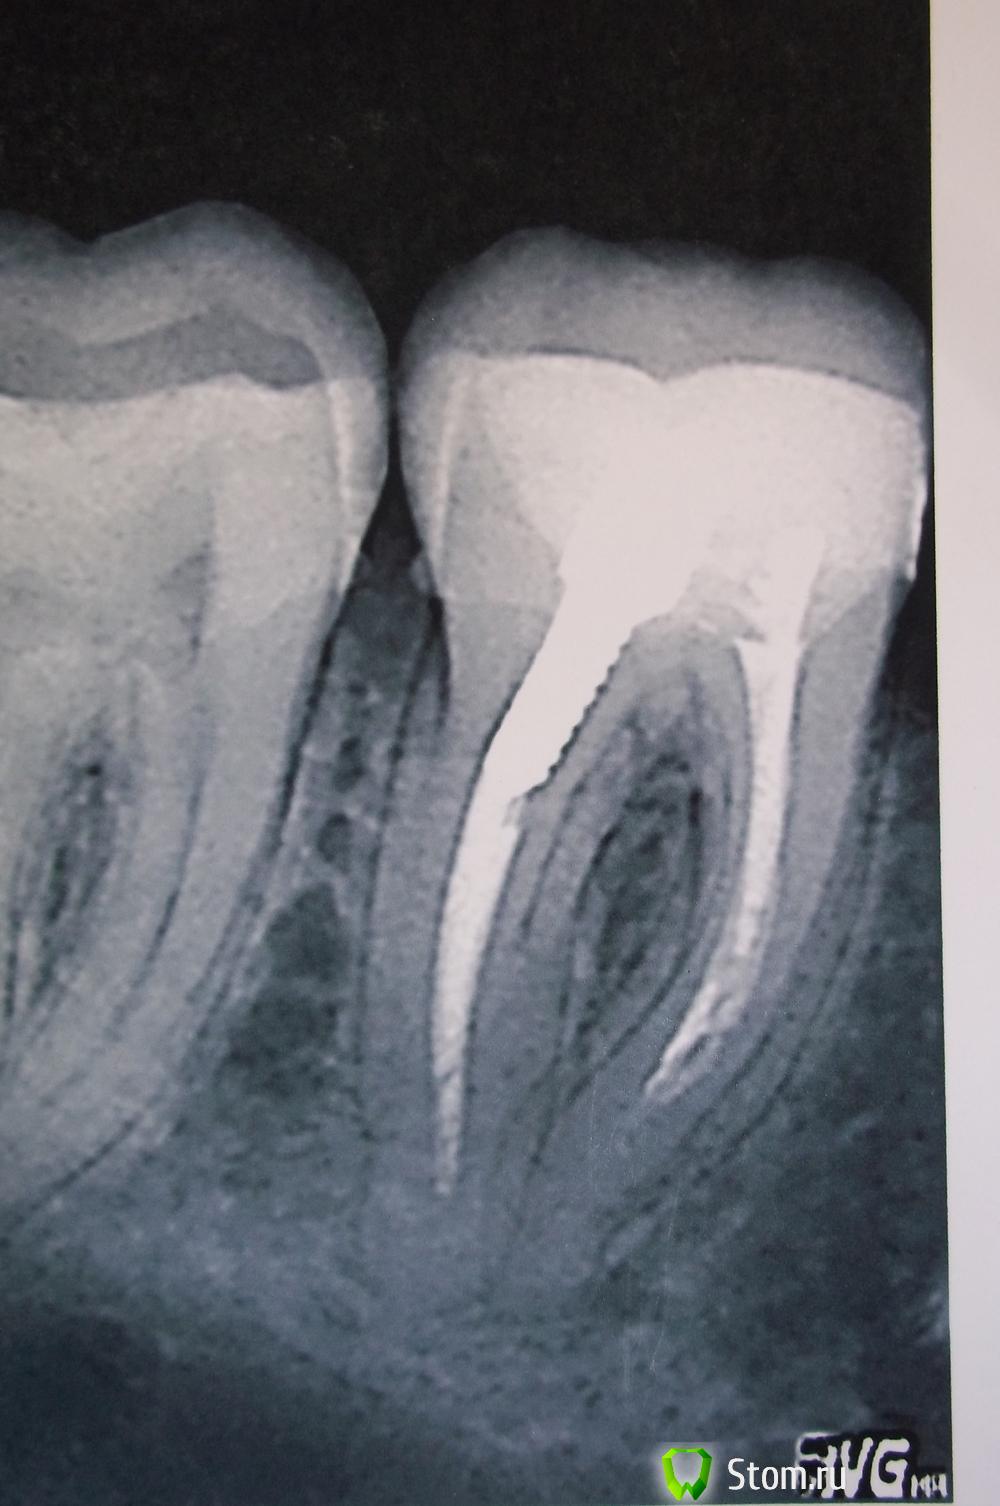

Satym Опубликовано 7 декабря, 2011 Поделиться Опубликовано 7 декабря, 2011 Здравствуйте. Подскажите, пожалуйста, мне. После лечения (нижней 6-ки) зуб заболел где-то через пол года. Врач снимок не делал, сказал, что не надо. Но, выяснилось, что канал не забит до конца. Это видно по снимку 1.jpg. Распломбировали этот не забитый канал, потом час, наверное, а может и больше в ручную иголкой "просверливали" этот канал, чтобы была возможность забить до конца. Положили какое-то лекарство. На следующий день распухла десна. Через неделю (точно не помню) пришла на повторный прием, положили лекарство с кальцием. Прошло полтора месяца, зуб болит, опухоль не спала. Врач сказал, что это лекарство не меняют. Надо ждать когда зуб заживет через несколько месяцев. На рисунке 2.jpg состояние зуба сейчас. Спасибо, Мария Ссылка на комментарий

annda Опубликовано 7 декабря, 2011 Поделиться Опубликовано 7 декабря, 2011 Снимок обрезан6но и на нём видно,что тоже не шибко до конца каналы распломбированы. Ссылка на комментарий

Scrabble Опубликовано 7 декабря, 2011 Поделиться Опубликовано 7 декабря, 2011 Надо вынуть ВСЁ из ВСЕХ каналов, посмотреть на предмет трещины-если нет её, перелечить, если есть-удалить. Ссылка на комментарий